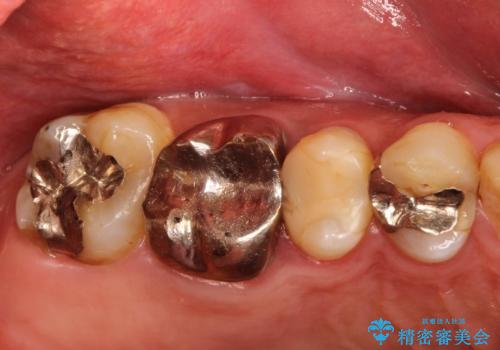

金属だらけの奥歯 根管治療のやり直しとセラミック化

金属の奥歯 → 白い奥歯 根管治療からのやり直し